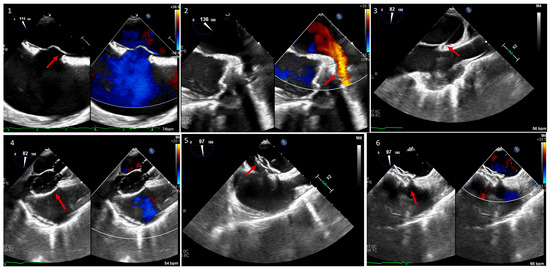

4. Transcatheter Edge-to-Edge Repair (TEER) of Systemic AV Valve

5. Paravalvular Leak Intervention